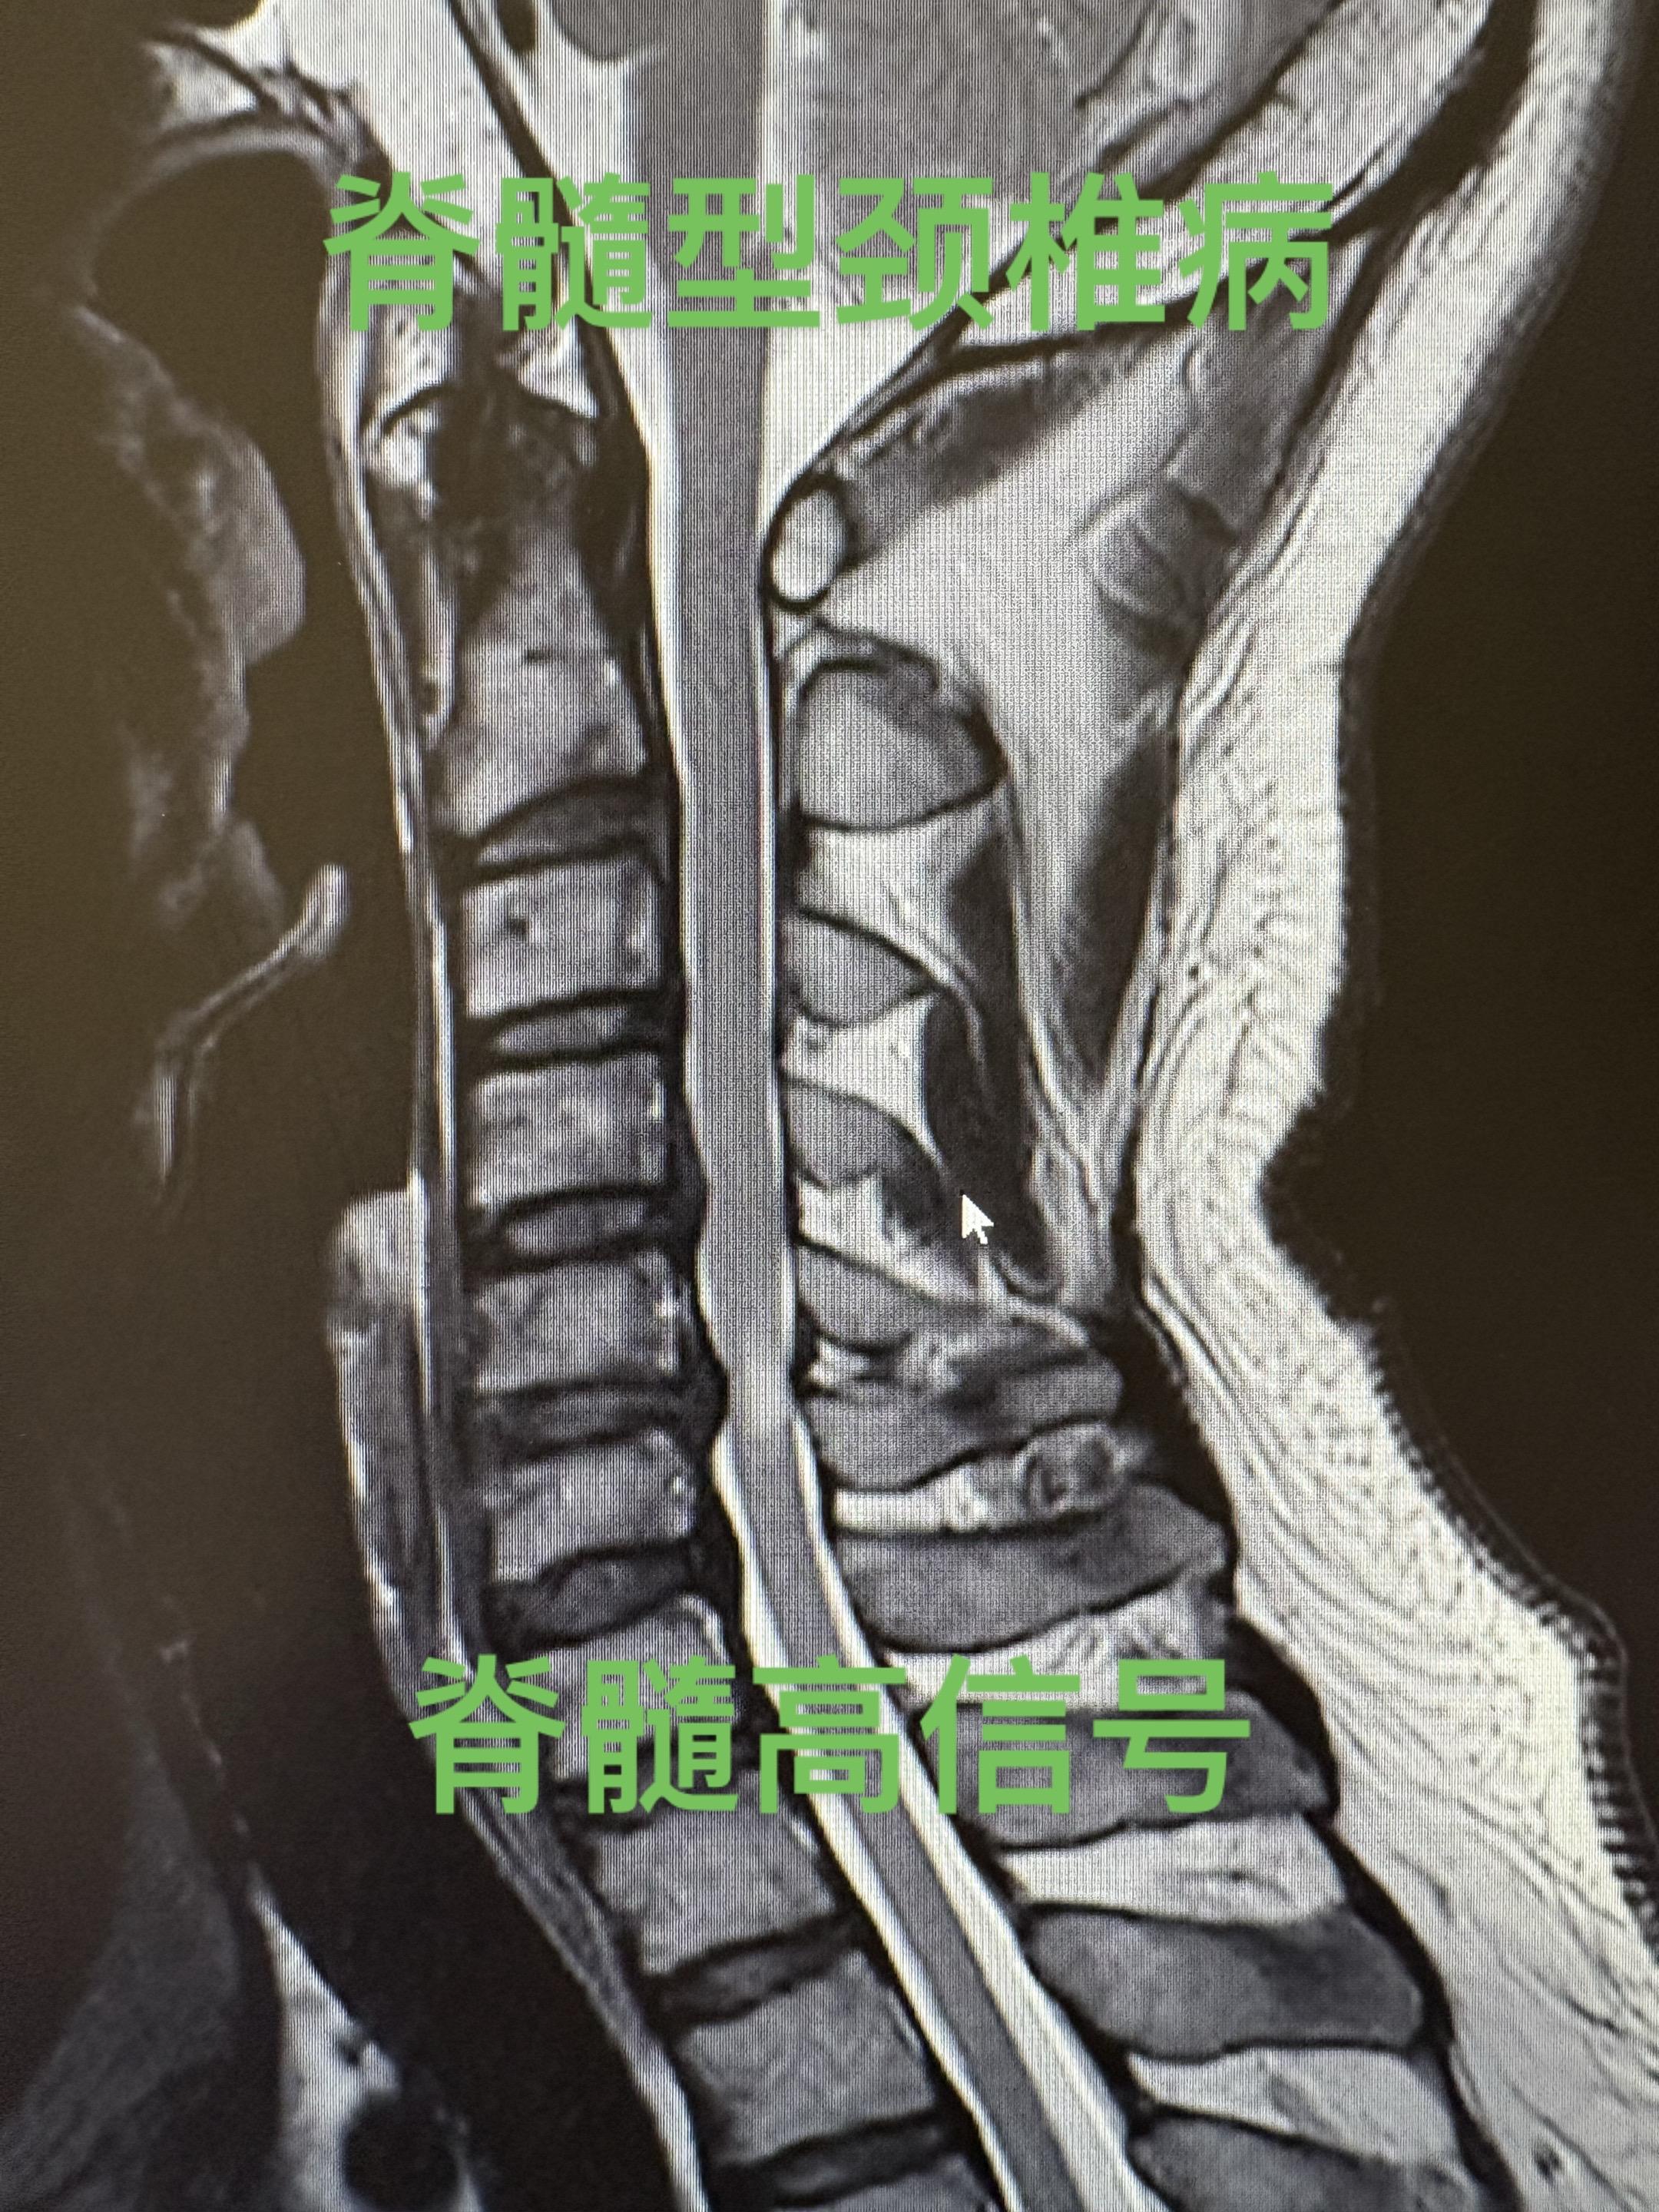

脊髓型颈椎病。外伤之后引起椎间盘突出,四肢麻木,行走有踩棉感,写字变丑...

脊髓型颈椎病。 典型症状:四肢麻木,行走像踩在棉花上。持筷夹物易落。手...

脊髓型颈椎病的治疗。脊髓型颈椎病的治疗策略 - [ ] 轻型:仅有神经...